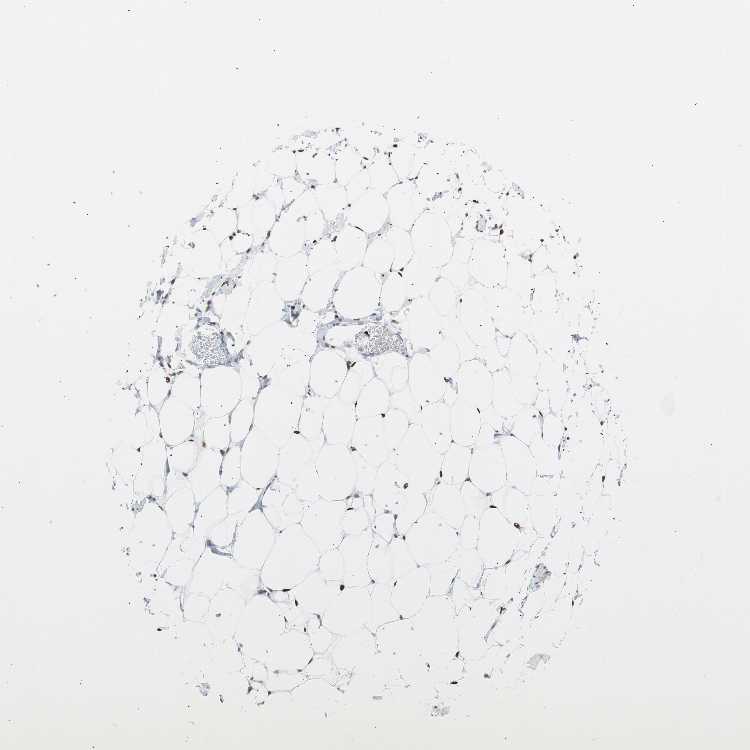

SOFT TISSUE 1 - Antibody stainingi

Antibody staining in the annotated cell types in the current human tissue is reported as not detected, low, medium, or high, based on conventional immunohistochemistry profiling in selected tissues. This score is based on the combination of the staining intensity and fraction of stained cells.

Each image is clickable and will lead to virtual microscopy that enables deeper exploration of all samples and also displays staining intensity scores, fraction scores and subcellular localization as well as patient and tissue information for each sample.

Antibody CAB004213

Fibroblasts Medium

Peripheral nerve Medium